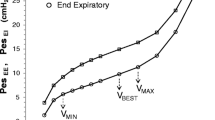

First, during deep sedation (Richmond Agitation Sedation Scale score of − 5), with patients in VCV mode, a special gastric feeding tube equipped with oesophageal balloon (Nutrivent Sidam, Mirandola, MO, Italy), previously deflated and secured with a three-way stopcock, was inserted through the nose/mouth till the stomach was reached. Afterwards, the balloon was connected through polyethylene tubes to a pressure transducer box (KleisTEK Engineering, Bari, Italy). The balloon was inflated at a volume of 4 ml, the intra-gastric position was confirmed by positive deflection during gentle external manual epigastric compression. Subsequently, the catheter was slowly withdrawn into the mid-lower third of oesophagus, as indicated by the appearance of cardiac artefacts on the oesophageal pressure waveform [4]. The calibration procedure was started to identify Vbest: the oesophageal balloon was progressively inflated with increasing volume from 0 to 8 ml, assuring a complete deflation before each inflation volume. At each volume, static end-expiratory and end-inspiratory Pes values were acquired by applying inspiratory and expiratory holds of 5 s. Hence, end-expiratory and end-inspiratory Pes to balloon filling volume curves were obtained and analysed. On the end-expiratory curve, the intermediate linear section was graphically identified together with its lower (Vmin) and upper (Vmax) inflection points. Vbest was chosen within this range of filling volumes as the smallest one associated with the largest respiratory tidal Pes swing (ΔPesT). Then, after the balloon calibration was completed, the validation occlusion test was performed with Vbest and V4, by applying two external compressions on the rib cage during an expiratory hold. Simultaneous deflections of airway (ΔPaw) and oesophageal pressure (ΔPes) were compared (occlusion validation test) [5, 18,19,20,21]: the test was positive if the ratio of oesophageal to airway pressure deflections (ΔPes/ΔPaw) was in the 0.8–1.2 range. Afterwards, sedation was reduced (Richmond Agitation Sedation Scale score of − 3/− 2) and, the patients, whenever able to trigger the ventilator, were switched to PSV. The oesophageal balloon was again progressively filled with volumes ranging between 0 and 8 ml, deflating it before each volume, and end-expiratory Pes values were collected during 3-s inspiratory and expiratory holds. During the hold, it was mandatory to check for the patient’s respiratory muscles relaxation, as proved by a flat and stable plateau of the Pes and airway pressure [4, 5]. After the end-expiratory Pes to balloon filling volume curve reconstruction and Vmin and Vmax identification [10], at variance from VCV, Vbest was identified as the oesophageal balloon filling volume associated with the highest ΔPesT to the related tidal volume (VT) ratio (ΔPesT/VT) (Fig. 1). As a matter of fact, during PSV, the VT is not constant as during VCV and absolute ΔPesT values might not be derived from best filling but rather from larger VT [24]. Finally, the occlusion test for validation in actively breathing patients was carried out as previously described to calculate ΔPes/ΔPaw ratio at Vbest and V4 [4, 5, 21].

Oesophageal balloon calibration in pressure support ventilation. Expiratory (hollow circles) and inspiratory Pes (hollow squares) to oesophageal balloon volumes curves are plotted. Also, the tidal Pes swing on tidal volume ratio at each balloon volume injected is depicted. Pes oesophageal pressure, Vmin and Vmax lower and upper inflection point of the expiratory curve, Vbest oesophageal balloon filling volume associated with the highest tidal Pes swing on tidal volume ratio (∆PesT/VT)